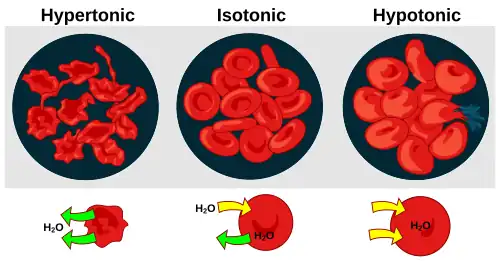

A typical human red blood cell has a disk diameter of approximately 6.2–8.2 μm[19] and a maximum thickness of 2–2.5 μm and a minimum thickness in the centre of 0.8–1 μm, being much smaller than most other human cells. These cells have an average volume of about 90 fL[20] with a surface area of about 136 μm2, and can swell up to a sphere shape containing 150 fL, without membrane distension.

Senescence

The aging red blood cell undergoes changes in its plasma membrane, making it susceptible to selective recognition by macrophages and subsequent phagocytosis in the mononuclear phagocyte system (spleen, liver and lymph nodes), thus removing old and defective cells and continually purging the blood. This process is termed eryptosis, red blood cell programmed death.[64] This process normally occurs at the same rate of production by erythropoiesis, balancing the total circulating red blood cell count. Eryptosis is increased in a wide variety of diseases including sepsis, haemolytic uremic syndrome, malaria, sickle cell anemia, beta-thalassemia, glucose-6-phosphate dehydrogenase deficiency, phosphate depletion, iron deficiency and Wilson's disease. Eryptosis can be elicited by osmotic shock, oxidative stress, and energy depletion, as well as by a wide variety of endogenous mediators and xenobiotics. Excessive eryptosis is observed in red blood cells lacking the cGMP-dependent protein kinase type I or the AMP-activated protein kinase AMPK. Inhibitors of eryptosis include erythropoietin, nitric oxide, catecholamines and high concentrations of urea.